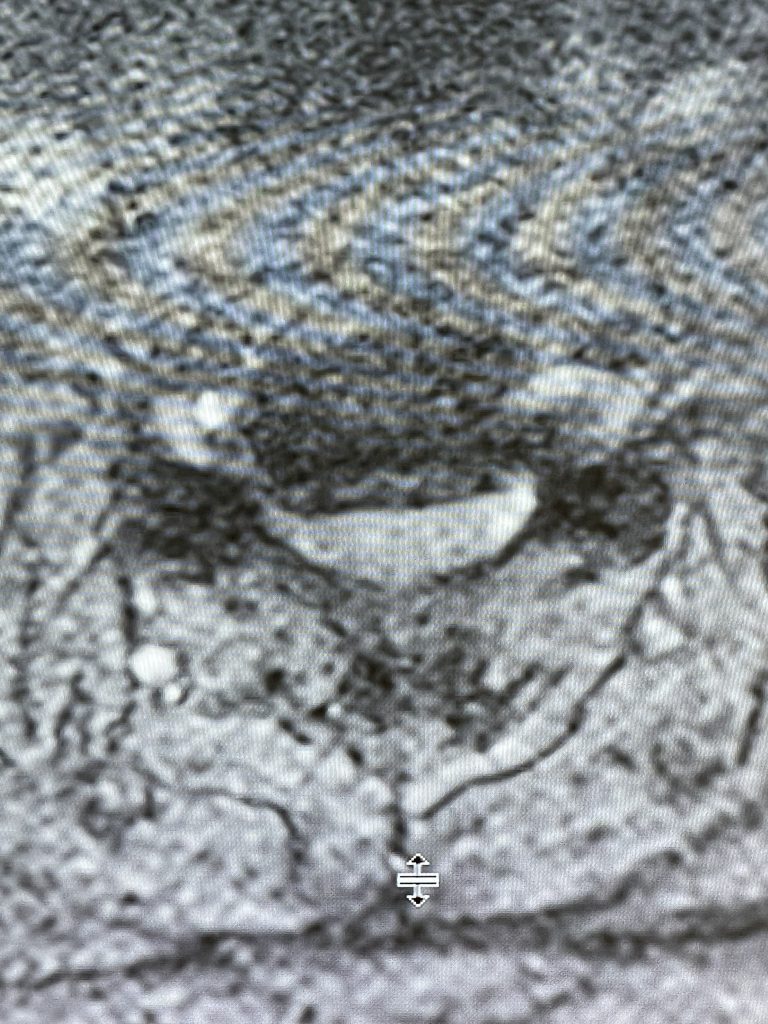

Fig 2: Axial T2-weighted MRI showing a large anterior osteophyte at C4-5 causing right greater than left spinal cord compression

Here is the case of a 51 year-old female who had a ten year history of severe neck pain with severe right arm pain, numbness, and weakness. She weighed over 300 pounds. She had failed all means of conservative management including medicines, physical therapy, chiropractic care, and epidurals. MRI demonstrated a reverse of the normal curvature of the cervical spine with large disc osteophyte complexes compressing the spinal cord (Fig 1). The C4-5 disc osteophyte was larger causing severe anterior compression of the spinal cord, worse on the right side (Fig 2). This correlated with the patient’s clinical findings. Therefore surgery was recommended. Patient underwent an anterior cervical discectomy and fusion with a plate from C4-C6. We were able to get her into a good position. Although there was a very deep exposure through the fat layer, it was not too bad to expose the face of the spine (Fig 3). Because there is less muscle, tissue planes open up actually easier sometimes particularly in women because of a relative decrease in muscle mass. The same goes for exposure of the lumbar spine. The majority of “herniated discs” in the cervical spine are actually bony protrusions we call osteophytes. After you clear away all the other cartilage that is the soft part of the disc, the way to get rid of that C4-5 osteophyte which acts like a sheet of bone at the posterior aspect of the disc space, is to drill it down to a fine shell and remove it with a special tool. This tool is called a Kerrison and has a very thin footplate that allows a plane between the osteophyte and dura which is being compressed and bites away this bone. The patient had good relief of her symptoms postoperatively.